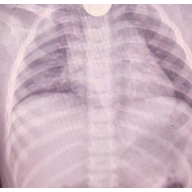

检查显示食管异物。

红网时刻新闻5月16日讯(通讯员 李俊)近日,长沙市妇幼保健院儿童消化营养专科门诊接诊了一位1岁患儿童童,据家长描述,童童不小心吞了一枚硬币,随后便出现了呕吐的症状。医生接诊后,完善了胸片+腹部平片,结果显示食管异物,以“食管内异物”收入儿内科。